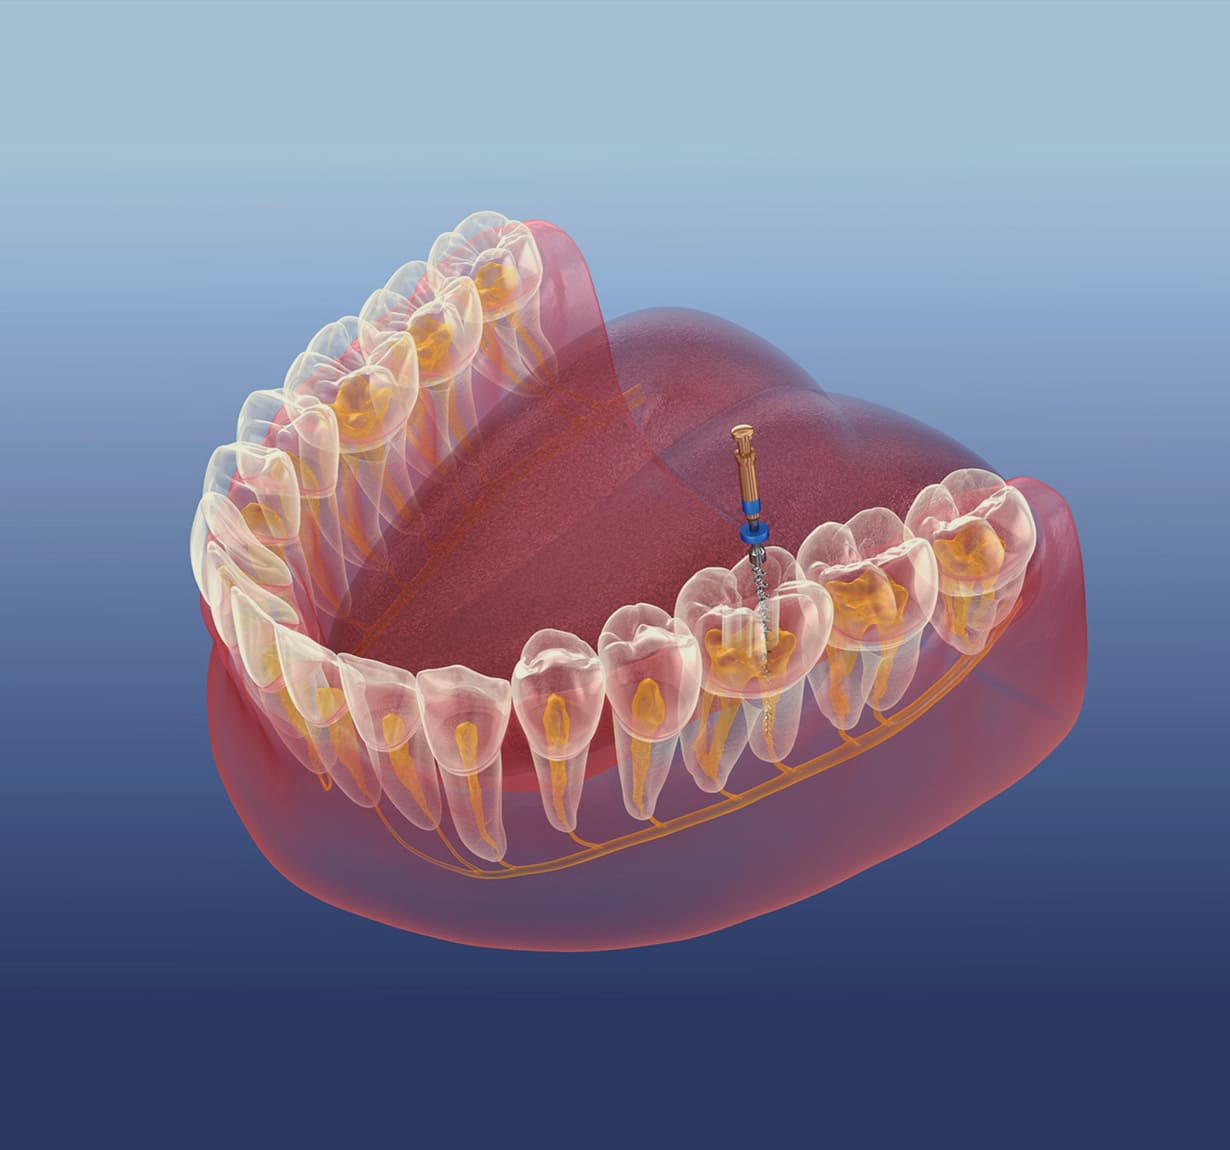

根管治療

虫歯や外傷などにより歯の神経に炎症が起きてしまったら、根管治療で細菌を除去します。他院で抜歯が必要と言われた場合でも、当院なら根管治療によって歯を残せるかもしれません。歯を失うと歯並びが悪くなるなど、さまざまなデメリットがあるので、可能な限り抜歯は避けたいものです。

根管治療は、まず局所麻酔をおこない、マイクロスコープを使って炎症を起こしている部分の細菌や汚れを除去します。清掃・消毒が終わったら、再び細菌が侵入しないよう神経が入っていた管に薬剤を詰めて治療を終了します。